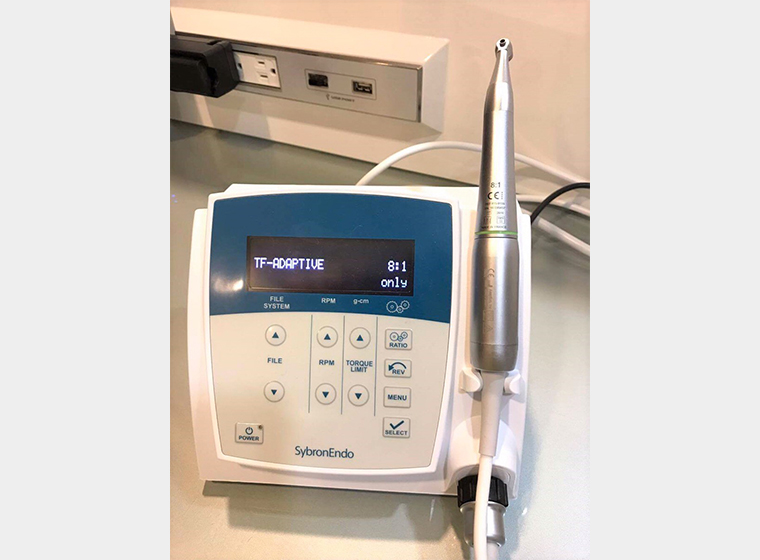

ニッケルチタンファイル

根管内を整えるために使用するのがファイルという、針のような形状の器具です。当院では適度なしなやかさや弾性があり、歯根にやさしく操作性が高いニッケルチタンファイルを採用しています。